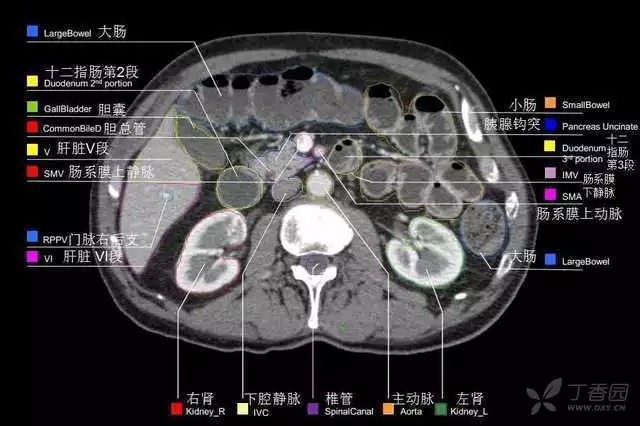

腹部肝脏高清CT断层的图谱

全腹部高清CT图谱,淋巴结彩色图谱,血管解剖图谱大汇总!

超声肝脏分叶及分段

肝脏分段和基本解剖学标志